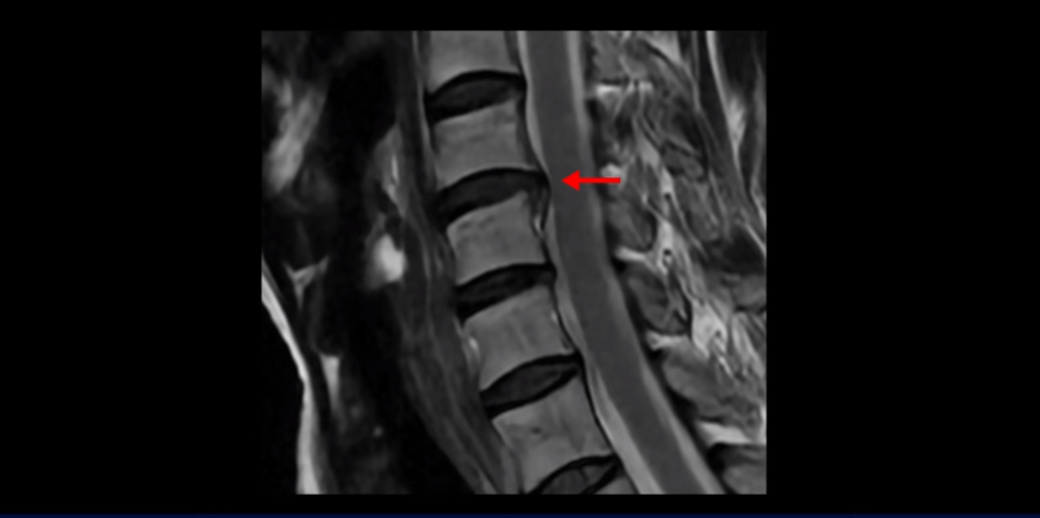

이분 MRI를 보면 세 마디의 퇴행성 목디스크가 있습니다. 4번 5번, 5번 6번과 6번 7번이 세 마디인데

디스크 파열은 4번 5번이 제일 심합니다.

중앙 오른쪽으로 수핵이 밀려 나와있고 밑으로 흘러 내려가 있습니다.

그런데 이 환자분의 방사통은 왼쪽 어깨와 팔입니다. 그래서 이 4번 5번 디스크 파열은 왼쪽 방사통의 원인이 아닌 걸로 보입니다. 6번 7번을 보면 디스크가 왼쪽으로 밀려 나와 있고, 뼈도 자라나 있습니다.

이렇게 뼈가 자라나 있으니까, 신경가지가 빠져나가는 추간공을 보면 여러 마디가 다 좁아져 있습니다.